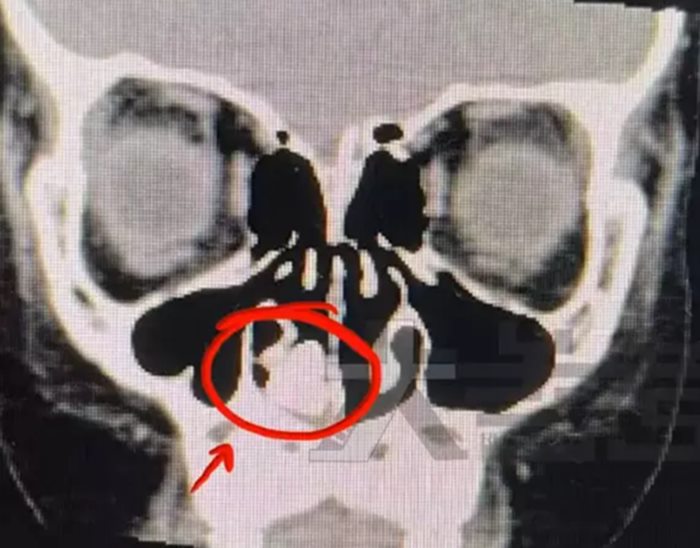

หลังจากทำซีทีสแกนบริเวณศีรษะ ก็ได้รับการยืนยันว่ามีก้อนอะไรบางอย่างติดอยู่ในโพรงจมูกของเด็กจริง ๆ แต่แพทย์ยังระบุไม่ได้ว่ามันคืออะไร และก้อนนั้นก็อยู่ในตำแหน่งที่สูงมาก จนแพทย์กังวลว่าอาจเกิดความเสียหายรุนแรงได้ถ้าจะพยายามนำออกมา แต่จะปล่อยทิ้งไว้ในจมูกของเด็กก็ไม่ได้เช่นกัน เพราะดูเหมือนก้อนดังกล่าวจะถูกล้อมไปด้วยหนอง หมายถึงเกิดการติดเชื้อขึ้นแล้ว